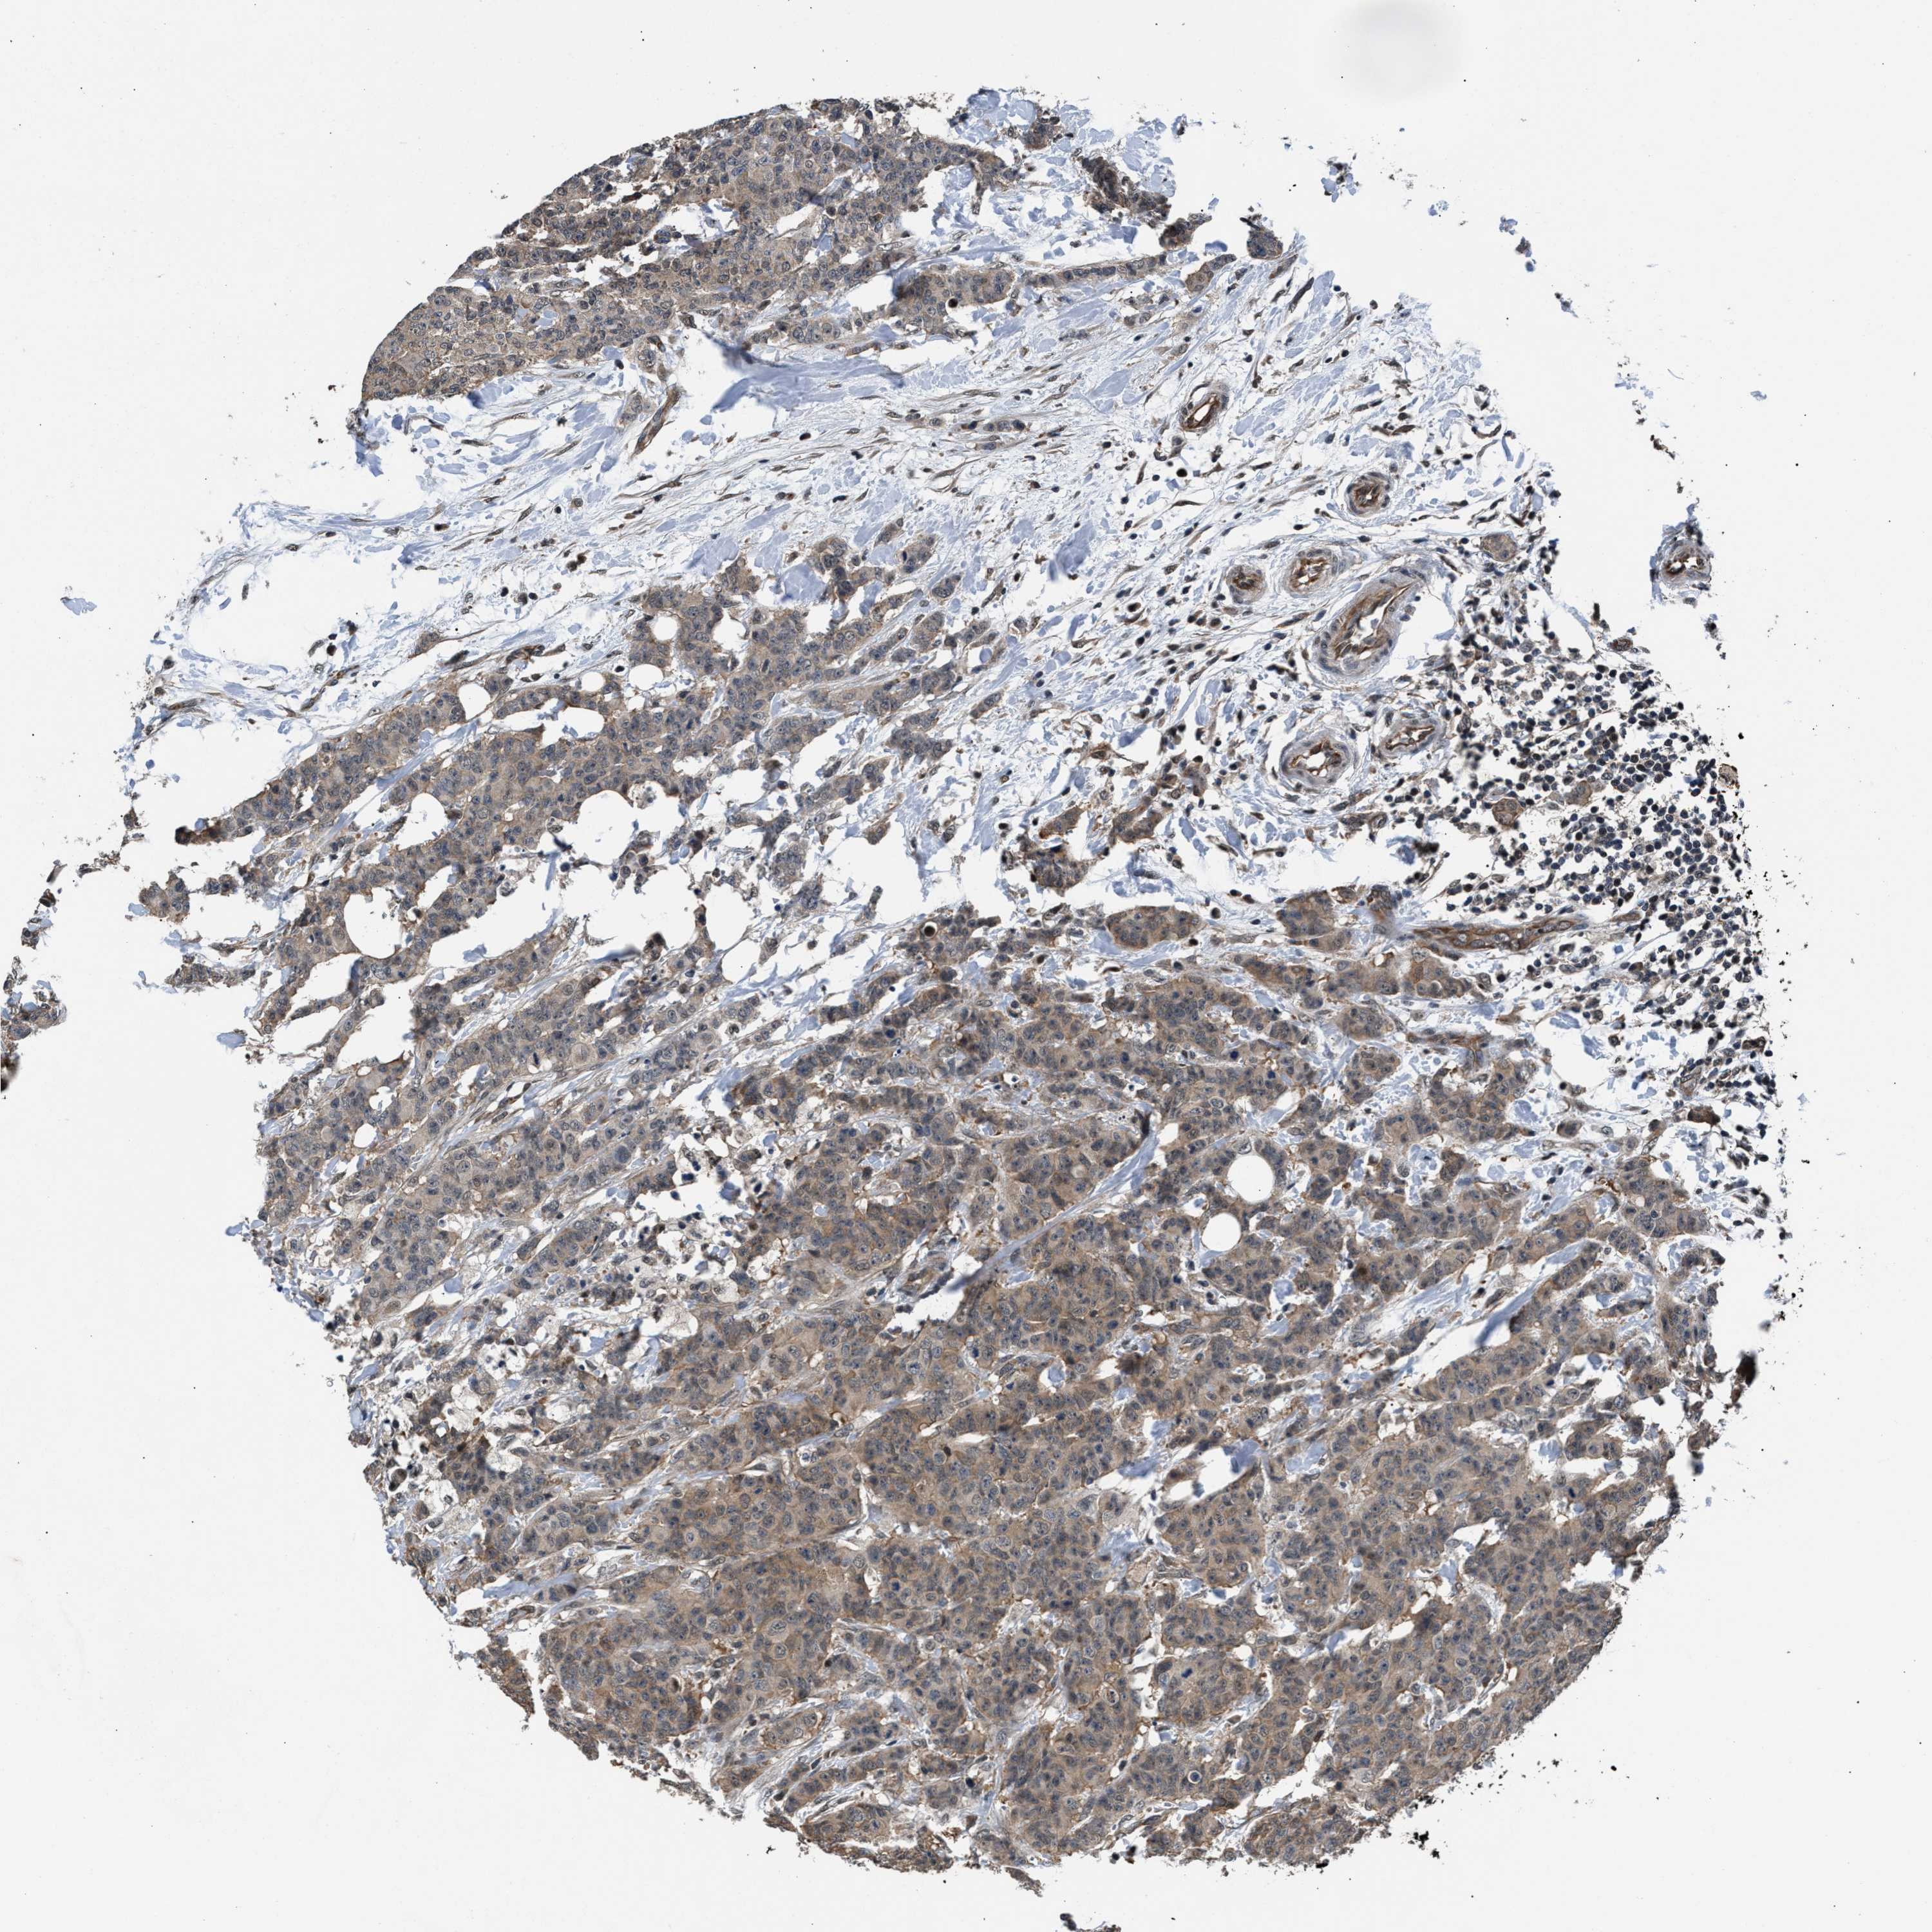

CANCER BREAST CANCER Show tissue menu

BRCA TCGA BRCA VALIDATION PROTEIN EXPRESSION